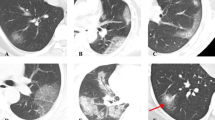

Chest CT

CT were acquired on 9 CT models (Table S1, supplemental data). The standardized report proposed by the French Society of Radiology (https://ebulletin.radiologie.fr/comptes-rendus-covid-19) was largely used by French radiologists across the participating centers. It includes a 5-scale score of severity (0% = absent; < 10% = mild; 10–25% = moderate; 25–50% = extended; 50–75% = severe; > 75% = critical) and a 4-point scale to categorize the risk of COVID-19: highly suspicious, compatible, not suspicious, and normal. Different patterns of COVID-19 lung lesions and their distributions were reported (ground-glass opacities, consolidations, and crazy paving) [24, 25].

Quantitative assessment of CT

An AI-based software tool for chest CT analysis (syngo.via CT Pneumonia Analysis prototype) from Siemens Healthineers (Version 1.0.4.2) was used to assess the severity of COVID-19. It automatically segments the lungs/lobes and delineates lung opacities (ground-glass and consolidations) based on a convolutional neural network trained with data manually labeled by expert radiologists [26]. If needed, lung segmentation was adjusted manually. Low attenuation areas were defined when below -950 HU (LAA-950).